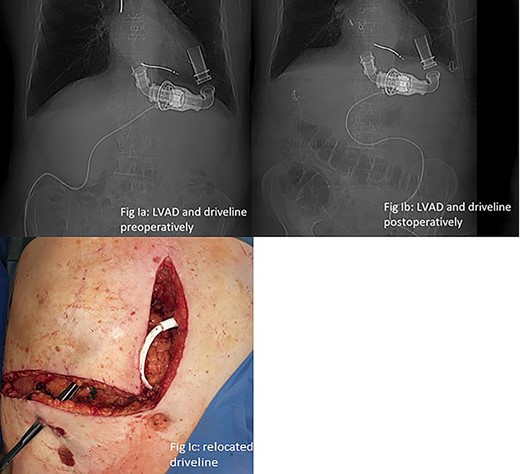

A 64-year-old male with severe ischemic cardiomyopathy underwent implantation of an LVAD (Heart mate II™, Abbott, Chicago, USA) in 2012. Decision of LVAD as destination therapy instead of heart transplantation was made due to history of hepatitis B infection, chronic kidney insufficiency and COPD. Patient remained in good condition with normal LVAD function. Further history included atrial fibrillation and pulmonary embolism. In 2019, hepatocellular carcinoma (HCC) was incidentally detected in the postero-lateral sector of the liver. Preoperative LiMax-Test [2] revealed good liver function (316 μ/kg/h), MELD XI Score was 15 without signs of portal hypertension. Staging revealed no distant metastases and confirmed local resectability (comp. Fig. 1).

LVAD-driveline was then dissected from scarring tissue, disconnected from its controller for 30 s and repositioned in the left upper quadrant. Circulation was maintained with the use of epinephrine and norepinephrine. Figure 2a and b show preoperative and postoperative driveline positions. Figure 2c shows relocated driveline position and former driveline exit.

(a and b) LVAD and driveline in preoperative and postoperative CT scan scout. (c) Relocated driveline during laparotomy, forceps in former driveline exit.